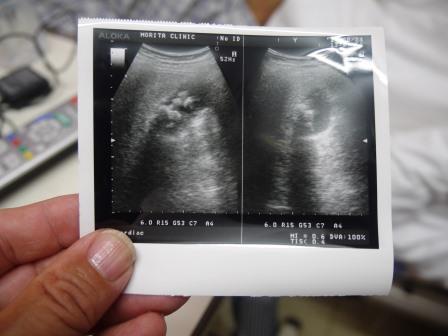

婦長さんに聞くところによるとエコーに「胆石」が山のように

写っているので、今後の対策のために「君津中央病院」を

紹介するとのこと。